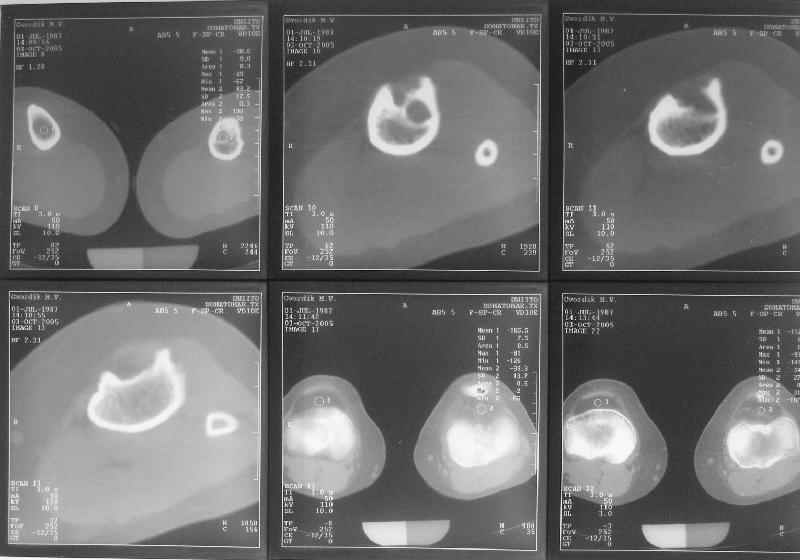

Жалобы у нее на появившиеся боли в колене при нагрузках. Признаков воспаления не было и нет, опухолевого роста также. Природа дефекта в области бугристости не очень понятна. Дополнительно сделали КТ и боковой снимок в максимальном разгибании - все в приложении.

Вас больше интересует коррекционная часть лечения, а меня - природа остеолизиса, потому, что механическая часть особого труда не представляет. Поэтому надо сначала, на мой взгляд поставить диагноз.

По-поводу деформации - Вы имеете дело с епи-метафизарной деформацией, скорее всего по причине преждевременного частичного закратия проксимальной зоныы роста большеберцовой кости.

Но прежде всего - дообследование, включая и биопсию.

На сегодня заключение рентгенолога - монолокальная монооссальная фиброзная дисплазия.

IMHO можно с достаточной уверенностью полагать, что это не опухоль и не инфекция, остальное с точки зрения тактики вряд ли значимо, поскольку лечение потребуется "синдромологическое", а не